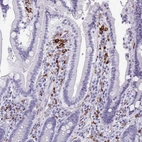

Immunohistochemistry analysis in human spleen and skeletal muscle tissues using HPA051974 antibody. Corresponding CD163 RNA-seq data are presented for the same tissues.